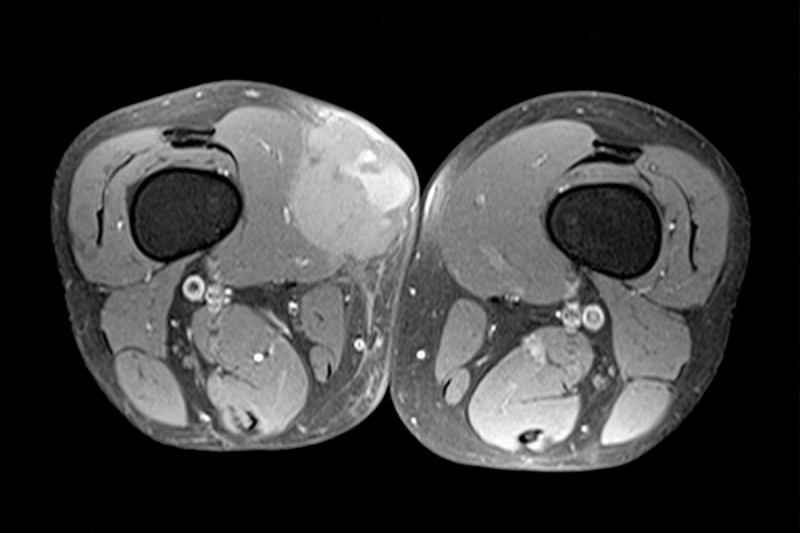

Credit: PHOTOSTOCK-ISRAEL / Science Source